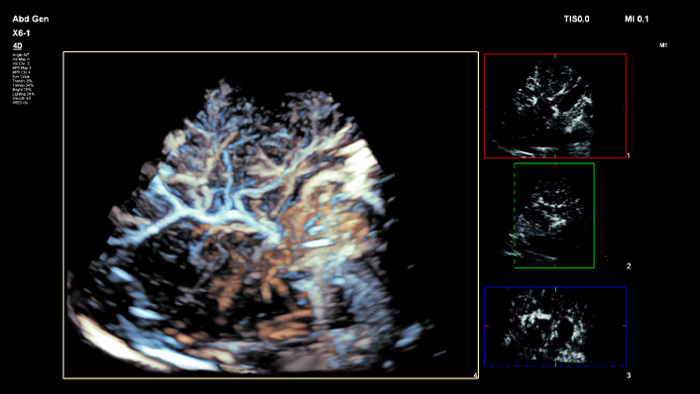

Ultrasound contrast agents can transform the role of ultrasound, allowing clinicians to study the enhancement patterns of liver lesions in real time. With Philips ultrasound, contrast enhanced ultrasound is seamlessly integrated into the standard workflow.

People come in many different shapes and sizes, with PureWave crystal technology you can improve penetration in difficult to scan body types, all while maintaining excellent detail resolution, Doppler sensitivity and contrast enhanced ultrasound (CEUS) performance.

PureWave crystal technology is the biggest breakthrough in piezoelectric transducer material in 40 years and is 85% more efficient than conventional piezoelectric materials, resulting in exceptional performance for all patient body types.